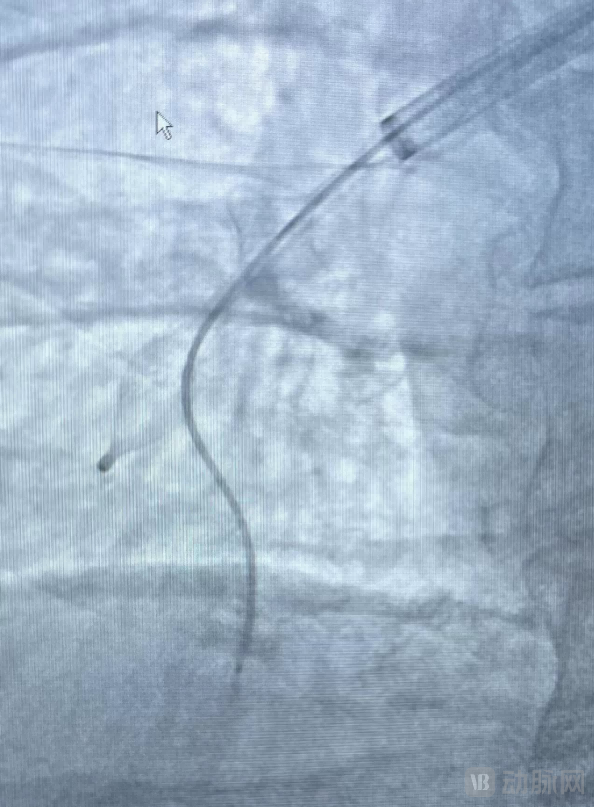

释放取栓支架